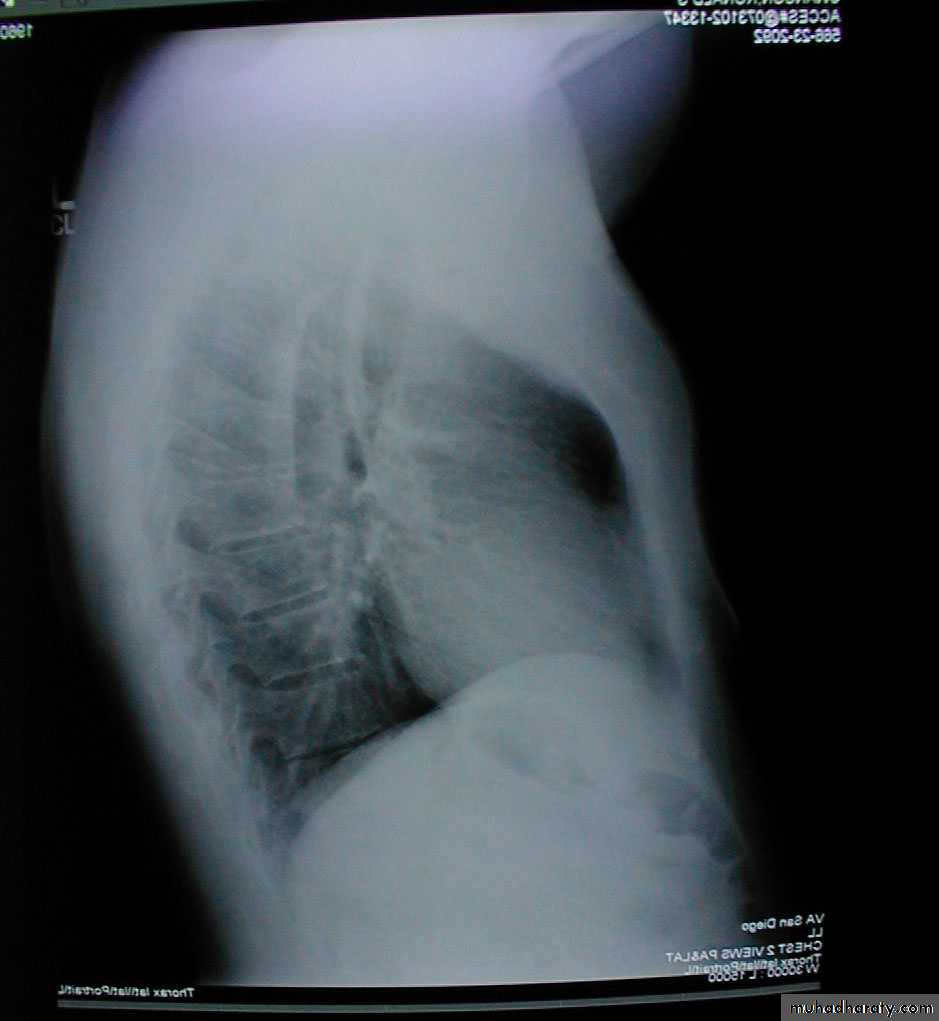

Barrel chest: Associated with emphysema and lung hyperinflation. Accompanying xray also demonstrates increased anterior-posterior diameter as well as diaphragmatic flattening.